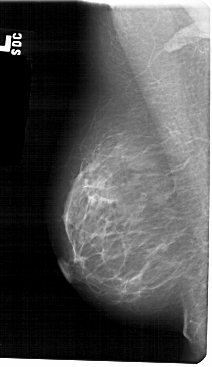

ics_version 1.0 filename A-1310-1 DATE_OF_STUDY 15 8 1995 PATIENT_AGE 48 FILM FILM_TYPE REGULAR DENSITY 1 DATE_DIGITIZED 7 7 1998 DIGITIZER HOWTEK 43.5 SEQUENCE LEFT_CC LINES 5491 PIXELS_PER_LINE 2851 BITS_PER_PIXEL 12 RESOLUTION 43.5 NON_OVERLAY LEFT_MLO LINES 5491 PIXELS_PER_LINE 3166 BITS_PER_PIXEL 12 RESOLUTION 43.5 NON_OVERLAY RIGHT_CC LINES 5491 PIXELS_PER_LINE 2926 BITS_PER_PIXEL 12 RESOLUTION 43.5 OVERLAY RIGHT_MLO LINES 5491 PIXELS_PER_LINE 2956 BITS_PER_PIXEL 12 RESOLUTION 43.5 OVERLAY |